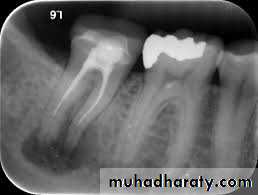

2. Working length Radiograph

Used to determine the length of the canal

3.Final instrumentation radiograph(Master Cone)

Taken with the final size file /files/

4.Final radiograph (Root canal after Obturation)

Taken after the tooth has been temporized.